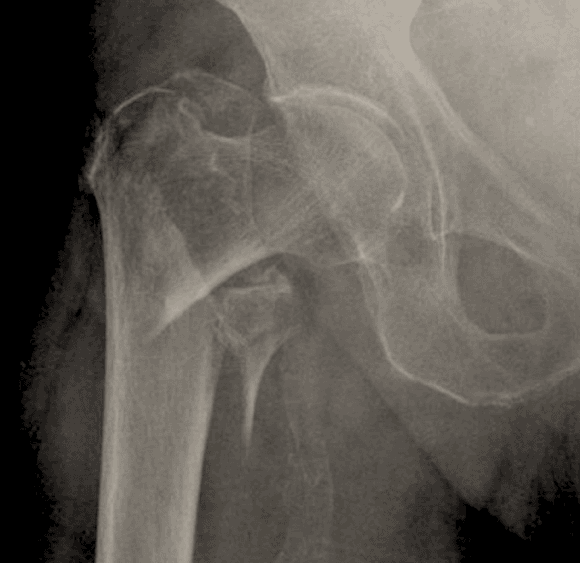

Basicervical femoral neck, intertrochanteric (IT), and subtrochanteric (ST) hip fx are different from femoral neck fractures in that they are extracapsular.

Extracapsular fractures, unlike intracapsular femoral neck fractures, have a low likelihood of blood supply disruption/AVN

The calcar femorale is an extension of cortical bone from the proximal shaft to the posteromedial femoral neck. It aids in weight distribution from the hip to the proximal femoral shaft.

The subtrochanteric region extends 5 cm below the lesser trochanter.